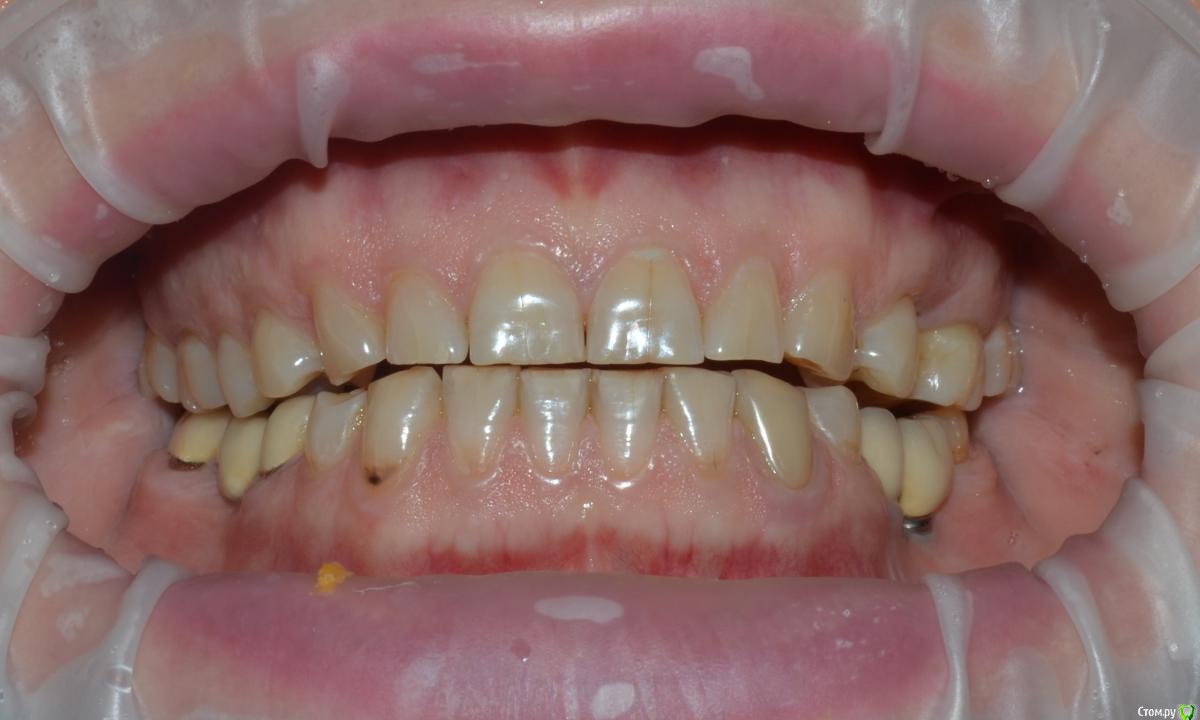

NazranDantist Опубликовано 21 мая, 2015 Поделиться Опубликовано 21 мая, 2015 (изменено) Коллеги поделитесь опытом. Какой план лечения предложить пациентке. Планируется тотальная работа что-нибудь из безметаловой технологии (E-max или претау, еще обдумываем). Вопрос, как выровнять оклюзионную плоскость, нужно ли прибегать к помощи ортодонта? Больше всего интересует первый сегмент, особенно зуб 15, висит слишком сильно. Или все таки стараться выйти из положения керамикой плюс хирургическое удлинение? Изменено 21 мая, 2015 пользователем NazranDantist Ссылка на комментарий

NazranDantist Опубликовано 4 сентября, 2015 Автор Поделиться Опубликовано 4 сентября, 2015 Продолжение кейса. Работа еще не закончена, зуб 25, 35, 36 - аббатменты на подходе, поэтому решили сделать после отпуска пациентки. Фото протокол не соблюдал, курс рубля прыгал, торопился в обменник . Вся работа - имакс на Цереке с редуцированием, фиксация - фронт на чойс, боковые - У-200. Ссылка на комментарий